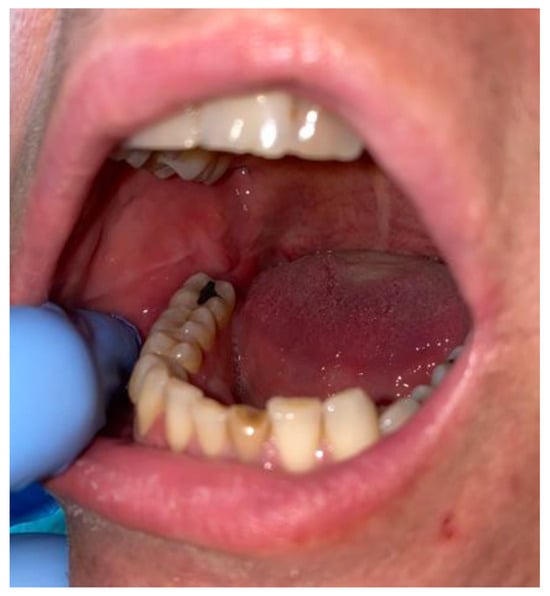

During the intraoral examination, in the right MRT area, a soft, well-defined mass measuring approximately 15 mm × 10 mm that was painless and had a smooth, fibro-elastic texture was observed. The soft-tumour mass did not bleb upon palpation, was symptomless and partially movable, and was partially well attached to the bone of the MRT. Adjacent teeth remained smooth and healthy, without any visible inflammation, irritation, or tumour infiltration. The tumour was elastic and covered with reddish-like swollen mucosa without any fluctuations; however, it contained some firm and solid structures. The mucosa covering the lesion lacked any abrasions, ulcerations, or any other atypical features (Figure 2).

Figure 2. Intraoral photograph of the right mandibular retromolar trigone soft-tissue tumour.